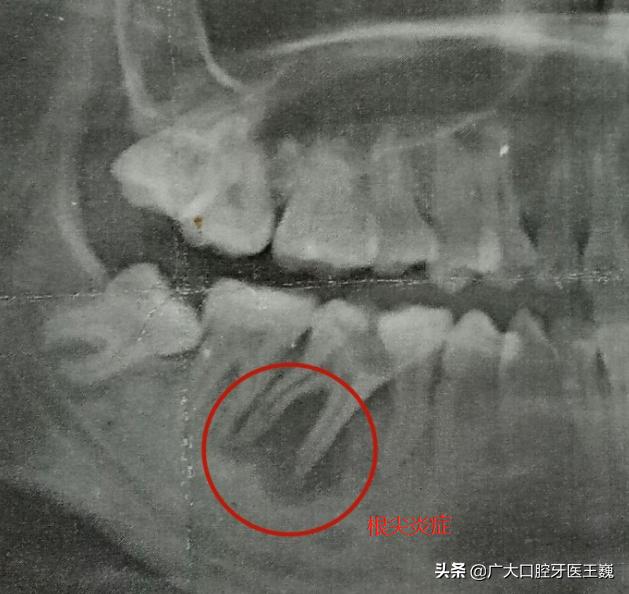

2、根尖炎引起的疼痛

临床上根尖炎的疼痛症状一般会表现为咬牙时出现疼痛,并且有牙齿伸长的感觉。

如果大家出现这种情况根据医生的指导服用抗生素/甲硝唑类的药物现行控制,紧接着就要到正规的口腔医院进行治疗。